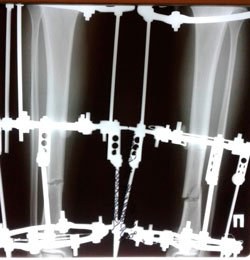

Исходник - 21 год.

Дата операции - 22.09.2020